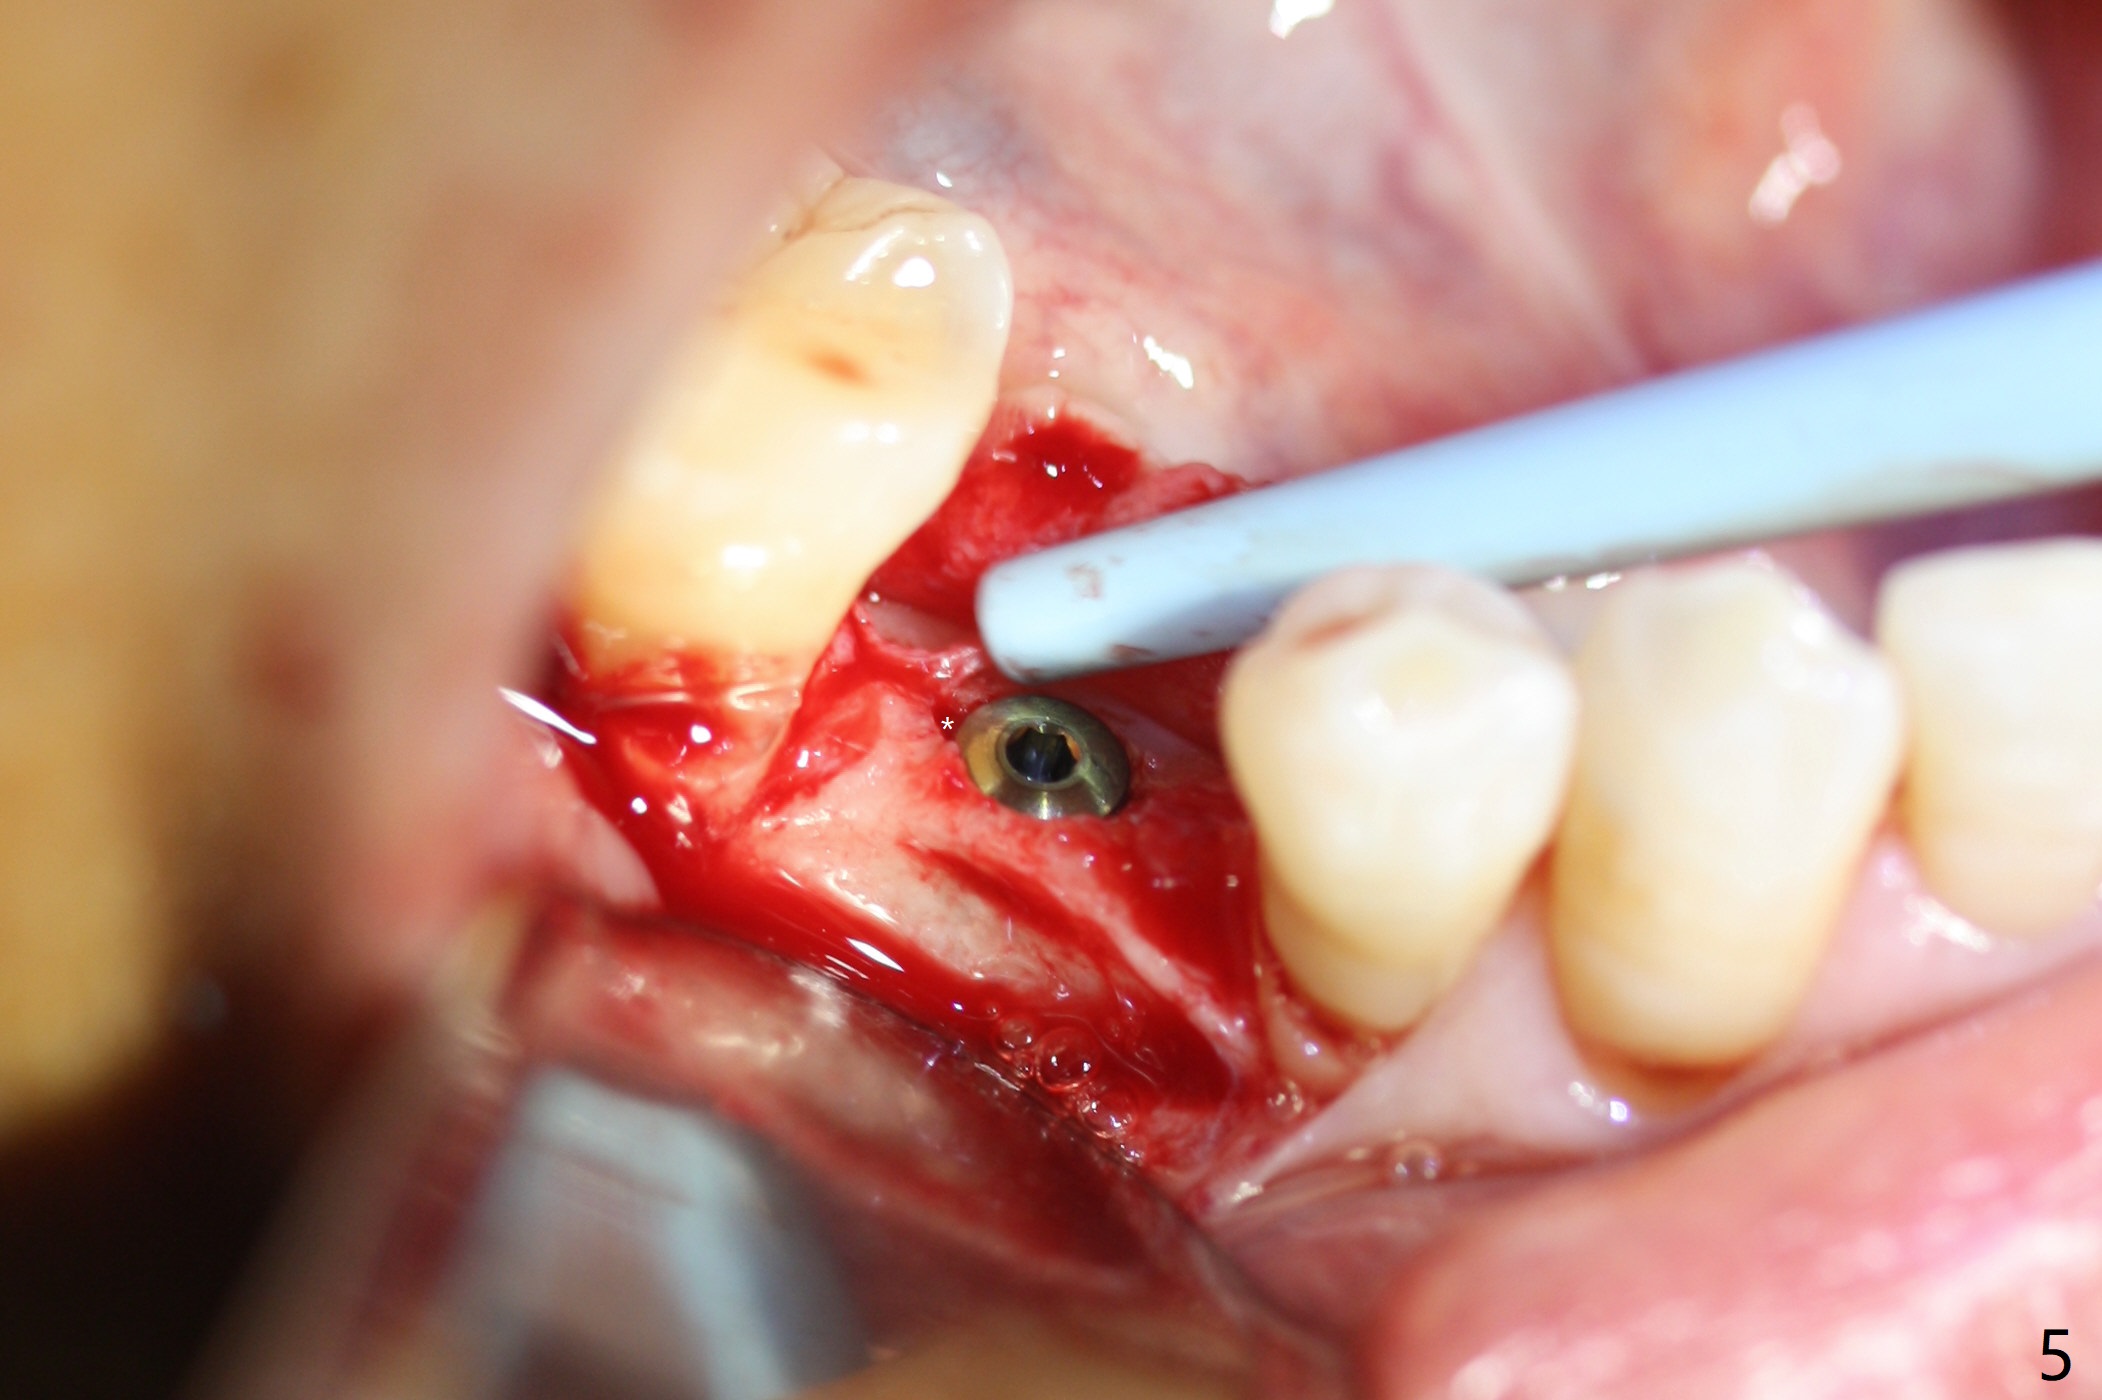

After incision the ridge at #29 is not so narrow as shown in Fig.1. But it is still intact, in contrast to what CBCT shows. Osteotomy is initiated with 1.2 mm drill, followed by 1/1.6, 1.3/2.3 and 1.7/3.1 mm DIO Bone Expanders. In fact mesial and distal crestal slots (BEB: bone expansion and bending) are created by using surgical fissure bur in order to insert the last bone expander in place (10 mm, Fig.2). Following 3.5 mm Cortical Tap, a 3.5x10 mm IS Implant is placed ~ 50 Ncm with clearance from the Mental Loop (Fig.3,4 red dashed line) and slightly subcrestal (Fig.5). The most distal part of the distal slot created for BEB is shown in Fig.5 *. Bone resorption is minimal 4 months postop (Fig.6,7). The implant was apparently placed in the middle buccolingually (Fig.8).